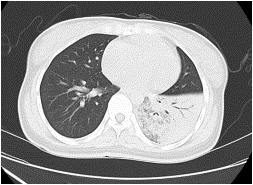

| 类型 | 常见病原菌 | 影像学特点 | 典型影像 |

| 细菌性肺炎 | 肺炎链球菌、肺炎克雷伯菌、流感嗜血杆菌等 | 病变范围较大,按肺小叶、肺段或肺叶分布;初期多为磨玻璃改变,进展为肺实变,少见肺萎陷和支气管扩张,胸膜渗出常见可出现胸腔积液、胸膜肥厚及肺脓肿 |  |